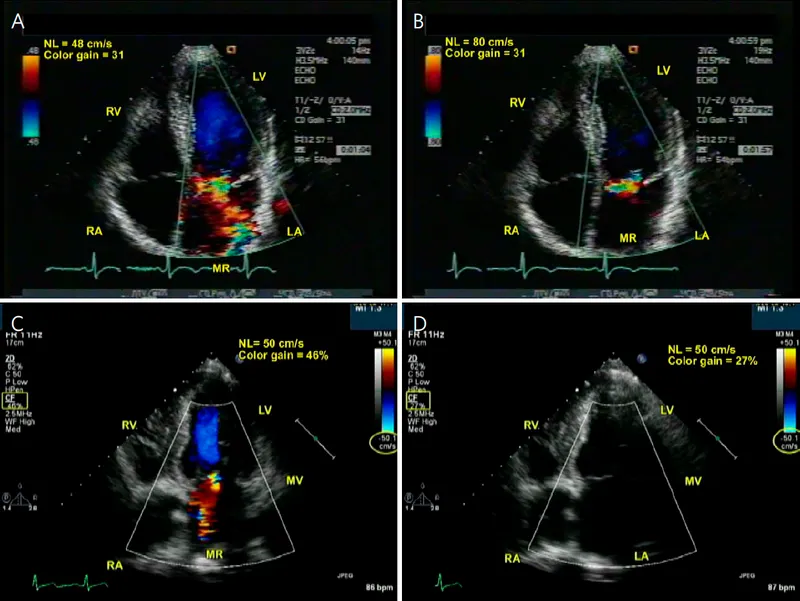

Mitral Regurgitation - The Backflow Problem

- Etiology: Most commonly from mitral valve prolapse; also ischemic damage to papillary muscles (post-MI), infective endocarditis, or rheumatic heart disease.

- Pathophysiology: Backflow into the left atrium (LA) causes volume overload in both the LA and left ventricle (LV).

- Leads to LA enlargement (↑ risk of atrial fibrillation) and eccentric LV hypertrophy.

- Eventually results in systolic dysfunction with a decreased ejection fraction.

- Murmur: Holosystolic, blowing murmur best heard at the apex, radiating to the axilla.

⭐ The intensity of the MR murmur does not correlate with its severity. A soft murmur can be severe, especially in acute MR where LA pressures are very high.